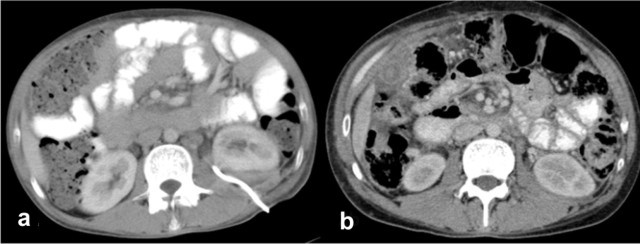

On evaluation, he was febrile (39°C) and had an 8x8 cm tender ballotable lump in the upper left abdomen. Ultrasonography of the abdomen showed a 12x8 cm left perinephric collection, and a percutaneous pig-tail catheter drain was placed under ultrasound guidance. It drained 600 mL of purulent fluid for the first two days and, thereafter, about 100 mL of hazy fluid per day. A bacterial culture of the fluid isolated alpha hemolytic Streptococci sensitive to ampicillin and aminoglycosides, and he was started on parenteral amikacin. The pig-tail catheter drain continued to drain about 100 mL fluid per day for more than 7 days although his fever subsided. A routine urine examination and a bacterial urine culture did not reveal any evidence of infection. Blood sugar was normal and HIV serology was negative. Electrocardiography and echocardiography were also normal. In view of the persistent drain output, the fluid was further investigated; the amylase level in the fluid was found to be 2,566 U/L (reference range: 20-96 U/L) and the corresponding serum amylase was 76 U/L. Contrast-enhanced computerized tomography (CECT) of the abdomen was carried out which showed dense foci of calcification in the head of the pancreas, a mildly prominent pancreatic duct with a 12.3x8.6 cm hypodense collection in the posteroinferior part of the left kidney, displacing it anteriorly and eroding its posteroinferior capsule (Figure 1). There was no evidence of fluid collection anywhere else in the abdomen. A diagnosis of chronic calcific pancreatitis with a left perinephric abscess was made and a gastroenterological opinion was sought. His serum parathyroid hormone and triglyceride levels were normal. There were no signs of pancreatic exocrine or endocrine insufficiency. He underwent endoscopic retrograde cholangiopancreatography (ERCP) but selective pancreatic ductal cannulation could not be achieved, possibly because of the dense calcification. A needle knife sphincterotomy of the ampulla of Vater was carried out in the direction of the 1 o’clock position, from the ampullary orifice. The patient had a reduction in drain output following this procedure. On the 11th day, the drainage stopped completely; repeat ultrasonography showed no residual collection and the pig-tail catheter drain was removed. He was asymptomatic on discharge and a follow-up CECT scan one month later showed complete resolution of the perinephric abscess (Figure 2).

Figure 2. a. CECT abdomen showing the percutaneous catheter drainage of the left perinephric abscess. b. Follow-up CECT showing resolution of the perinephric abscess. |